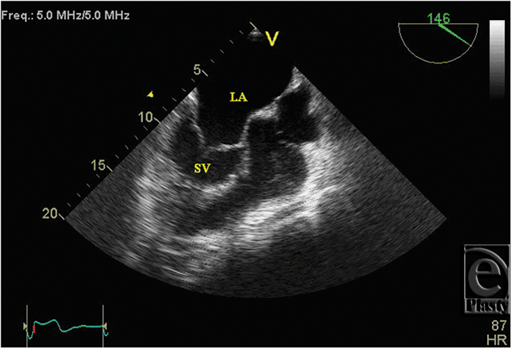

Initial 2D echocardiogram showed severe mitral valve regurgitation with a left ventricular ejection fraction of 35%. Furthermore, the valvular anatomy appeared peculiar; based on right ventricle (RV) and left ventricle morphology, CCTGA was suspected. A transesophageal echocardiography (TEE) was performed for further evaluation. It confirmed our diagnosis of CCTGA. Also, the (TEE) showed a hypertrophied RV and severe systemic AV (SAV) valve regurgitation (Figs 1 and 2). There was no evidence of an atrial septal defect, VSD, or patent ductus arteriosus. An MRI (magnetic resonance imaging) was performed to elucidate the anatomy. It affirmed the diagnosis of CCTGA with a trileaflet SAV that demonstrated severe regurgitation from the systemic ventricle (SV) to left atrium (Figs 3-6). Because of the patient's symptoms and severity of the regurgitation of the SAV, we decided to perform SAV replacement. Preoperative cardiac catheterization showed left dominant coronary circulation with left circumflex and a ramus intermedius originating from left cusp through separate ostia (Figs 7 and 8). Left anterior descending artery originated from proximal right coronary artery through a single ostium from right coronary cusp (Figs 8 and 9). No obstructive coronary heart disease was found and the patient proceeded to surgery.

![]() |

| Figure 1. Transesophageal echocardiogram showing hypertrophied SV and dilated LA. LA indicates left atrium; SV, systemic ventricle. |